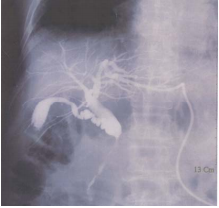

48 一位 80 歲男性,最近二星期來出現茶色尿(tea color urine),皮膚黃疸,體重減輕,Bil(T/D)level 10.7/10.6 mg/dL,則下圖為那一種檢查?

(A)內視鏡逆行性膽道胰管攝影(Endoscopic retrograde cholangiopancreatography) (B)上消化道攝影(Upper GI series) (C)經皮穿肝膽道攝影(Percutaneous transhepatic cholangiography) (D)泌尿道腎盂攝影